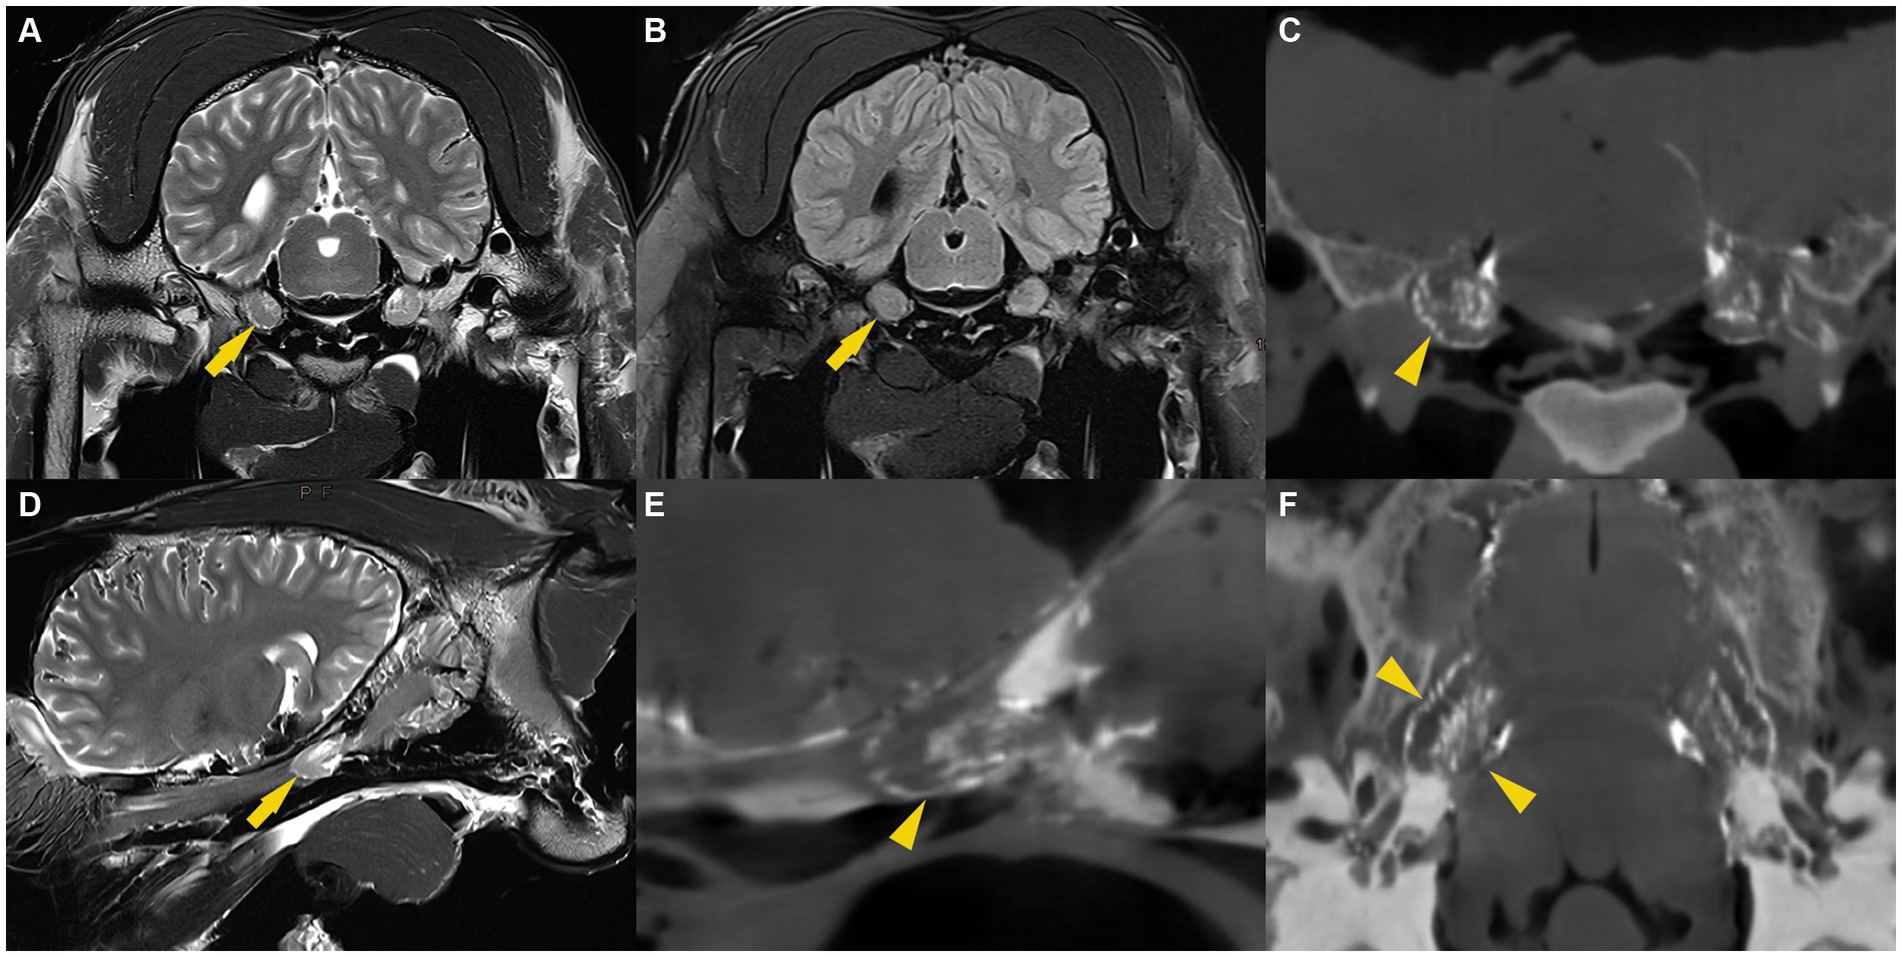

Las imágenes de RM fueron evaluadas por un radiólogo certificado (C.P.) y permitieron consistentemente la visualización bilateral de la acumulación de líquido de intensidad de señal similar al LCR alrededor del ganglio trigémino. El patrón de distribución del LCR fue similar en todos los especímenes. En las imágenes transversales transversales de EET ponderadas en T2, una sutil línea de demarcación fluida rodeaba el ganglio trigémino. Además, se identificó una cantidad variable de líquido, dispuesto en un patrón trabecular, entre los haces de fibras nerviosas y el ganglio del trigémino. Ambas características distintivas fueron más pronunciadas en la cara axial del ganglio trigémino. Estas imágenes se compararon con secuencias FLAIR ponderadas en T2 en plano transversal, que también mostraron una señal de fluido suprimida que rodea el cerebro, el cerebelo y el ganglio trigémino (Figura 2). Esto confirmó la naturaleza del líquido que rodea el ganglio trigémino por la líquido cefalorraquídeo. En las imágenes sagitales, se detectó una señal de fluido hiperintensa en las secuencias T2 de TSE y una señal de fluido suprimida en las secuencias FLAIR ponderadas en T2 alrededor del ganglio del trigémino. La línea fluida que rodea la cara rostral del ganglio trigémino mostró consistentemente una forma cónica y convexa. Caudalmente al ganglio del trigémino, pero dentro de la cueva del trigémino, el líquido estaba dispuesto en un patrón trabecular que se asemejaba al patrón de distribución en las imágenes transversales (Figura 2).

En las imágenes CBCT, el material de fundición radiopaca era reconocible como una línea hiperintensa y bien delineada que rodeaba el ganglio del trigémino y se encontraba dentro de la cueva del trigémino. Para cada espécimen, se compararon las imágenes de RMN (pre-cisternografía) y las imágenes CBCT (post-cisternografía). La distribución del material de fundición radiopaco dentro de la cueva del trigémino fue similar a la distribución del LCR en las imágenes de RM, lo que sugiere que el material de fundición se había inyectado en el espacio subaracnoideo (lleno de LCR) (Figura 2). En dos cuevas del trigémino de dos cabezas de cadáveres diferentes, la forma del molde radiopaco difiere significativamente de las otras 10 cuevas del trigémino, incluidas las contralaterales. Allí, el material de fundición tenía márgenes indefinidos e irregulares y no se extendía tan rostralmente como en los otros. Esto presumiblemente fue el resultado de una perforación inadvertida de las meninges durante la inyección del material de fundición.